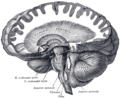

الشكل 1b: صورة تصوير الرنين المغناطيسي تبين منظراً mid-sagittal للمخ البشري، ويبدو فيه المخيخ باللون البنفسجي من , , , http://www.marefa.org/index.php/صورة:Neuro_logo.png

المخيخ Cerebellum هو القسم الكروي الأصغر الذي يقع أسفل نصفي الكرة المخيتين في الدماغ ، يهتم المخيخ بشكل أساسي بوظائف التوازن و تنظيم الوظائف الحركية. يقع أسفل النصفين الكرويين في الجهة الخلفية للمخ ويتركب من فصين أيمن وأيسر يصل بينهما فص ثالث.